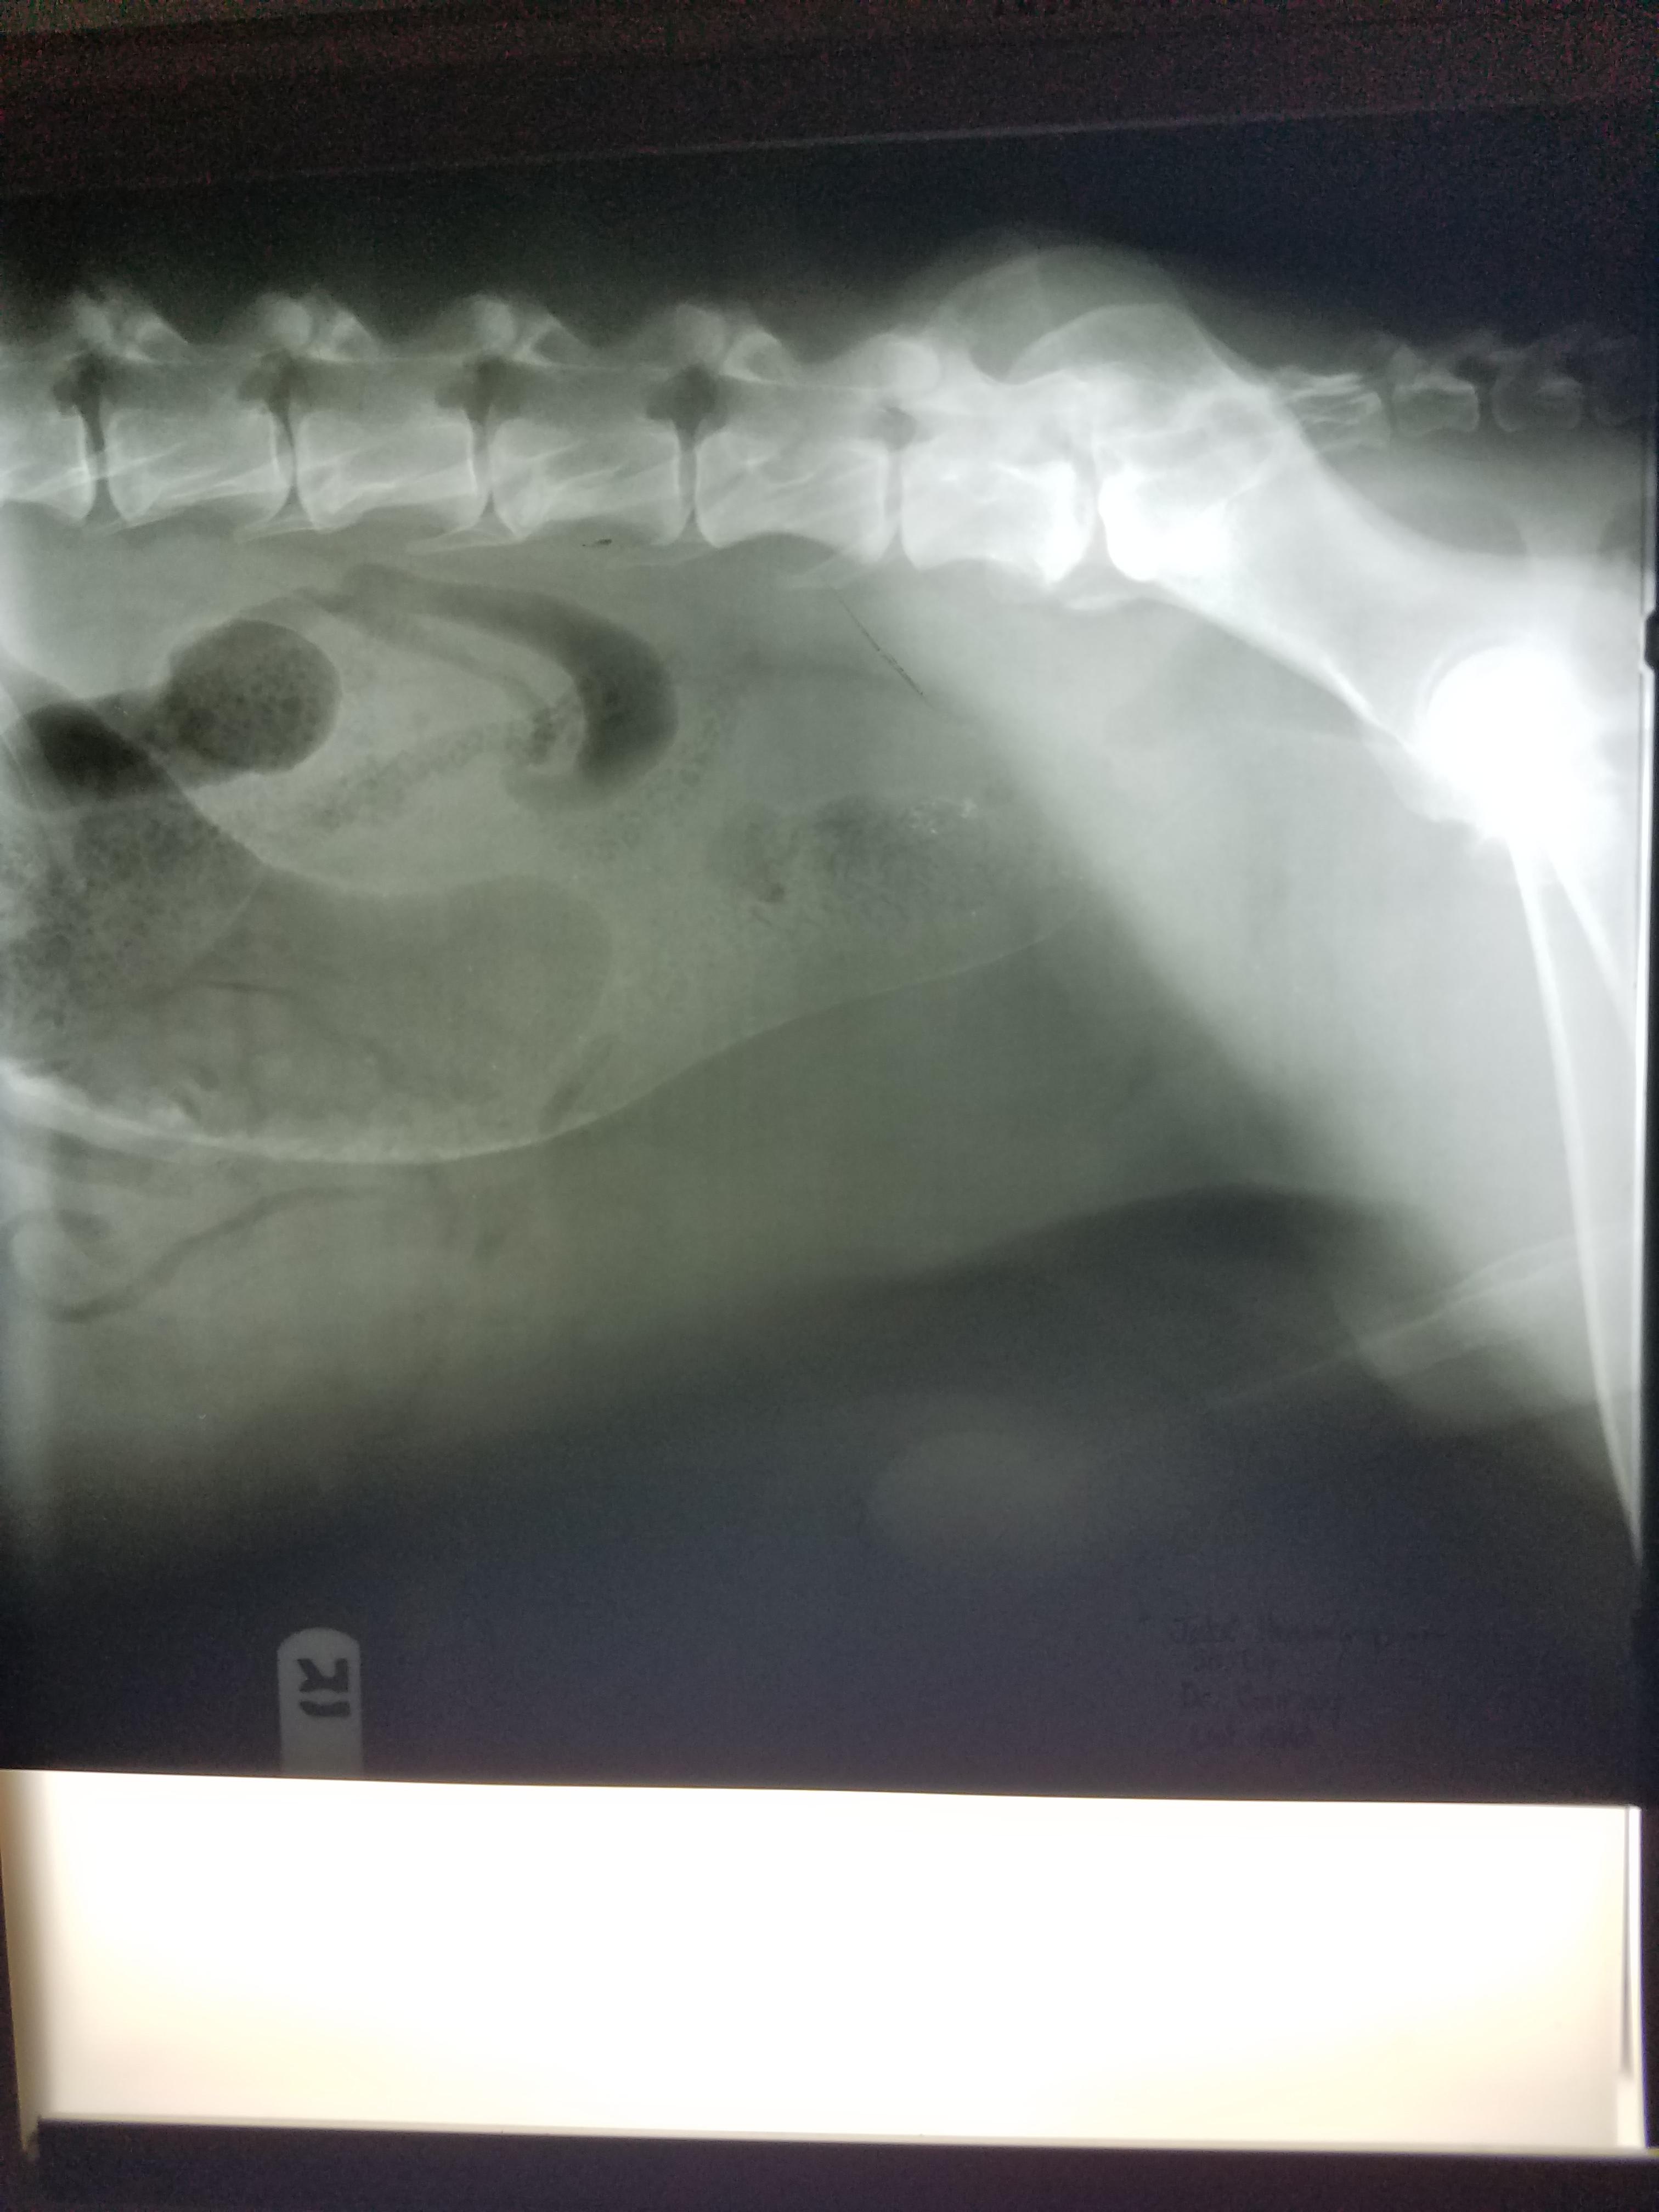

Senior dog has enlarged testicles, swollen legs, and high WBC. Is it cancer?

Pet's info: Dog | German Shepherd | Male | 10 years and 7 months old | 98 lbs

I keep getting conflicting answers. Vet said he has colorectal or prostate cancer. Two here say gas and feces build up. His testicles are like orange size and Dr said swell in back legs is called edema compromised circulation. Vets here don't have the patient and can go only by the attached x-rays. He also has impacted fistulas. Dr recommend euthenasia. Gas build up isn't the same as cancer Blood work shows wbc 43.35 see attached

It sounds like prostatitis and/or cancer. I'm not exactly sure what your question is. We don't have enough information to be able to guide you to a decision. I do not think it is simple gas/constipation. The fistulas and the size of the testicles is very concerning. I think you should consider taking him to an internal medicine specialist for a consult. ( https://www.gcvs.com/service/internal-medicine/ ) ( https://urbananimalveterinary.com/services/internal-medicine/ )